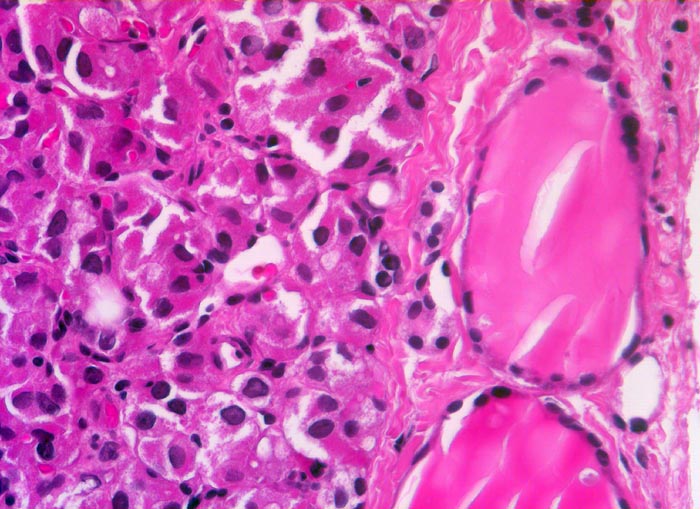

follikuläres Schilddrüsenkarzinom

Schilddrüse

Rechts im Bild zwei normale Follikel mit flachem Epithel und reichlich Kolloid. Die neoplastischen Follikel links im Bild sind sehr klein und enthalten kaum Kolloid. Die Tumorzellen haben vergrösserte polygonale Kerne und reichlich Zytoplasma.

Seit zirka 10 Jahren ist beim Patienten eine Struma bekannt. Jetzt sucht er den Hausarzt auf, weil er den Eindruck hat, die Schilddrüse sei grösser geworden. In der Ultraschall-Untersuchung wird ein Knoten im rechten Schilddrüsenlappen festgestellt, der relativ scharf vom angrenzenden Gewebe abgesetzt ist. Die Feinnadelpunktion ergibt eine follikuläre Neoplasie; eine Unterscheidung zwischen einem follikulären Adenom und einem follikulären Karzinom ist zytologisch jedoch nicht möglich. Es wird eine Hemithyreoidektomie durchgeführt und nach der Diagnosestellung eines follikulären Karzinoms eine Resthyreoidektomie angeschlossen.